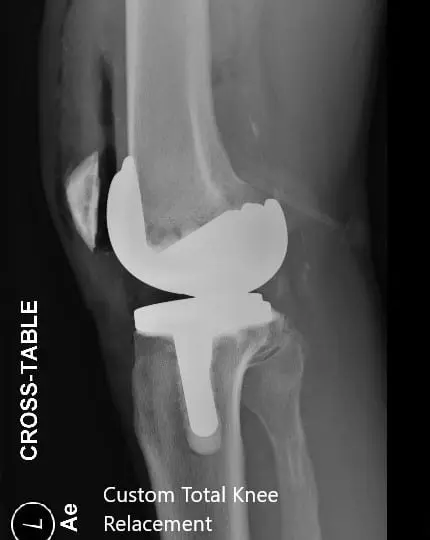

Postoperative X-ray of the left knee showing AP and lateral views

Postoperative X-ray of the left knee showing AP and lateral views - img 2

PROSTHESIS: Custom tibial tray with a custom femoral component with 6-mm polyethylene insert with a 32 -mm patella.